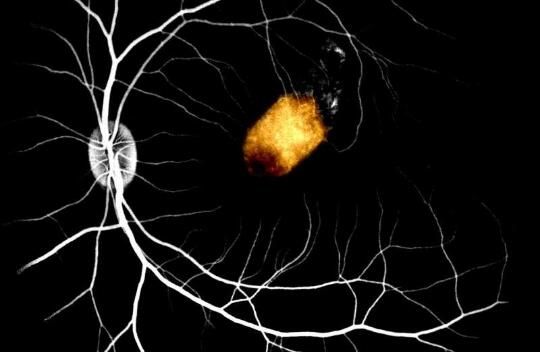

再生医学网获悉,近日,一项刊登在国际杂志Stem Cell Reports上的研究报告中,来自西奈山医院等机构的科学家们通过研究发现,将来自人类尸体的视网膜细胞(retinal cells)移植到灵长类动物模型的眼睛后,这些视网膜细胞竟然能够得以存活,这一研究突破有望未来帮助研究人员开发治疗人类失明症的新型细胞疗法。 ......